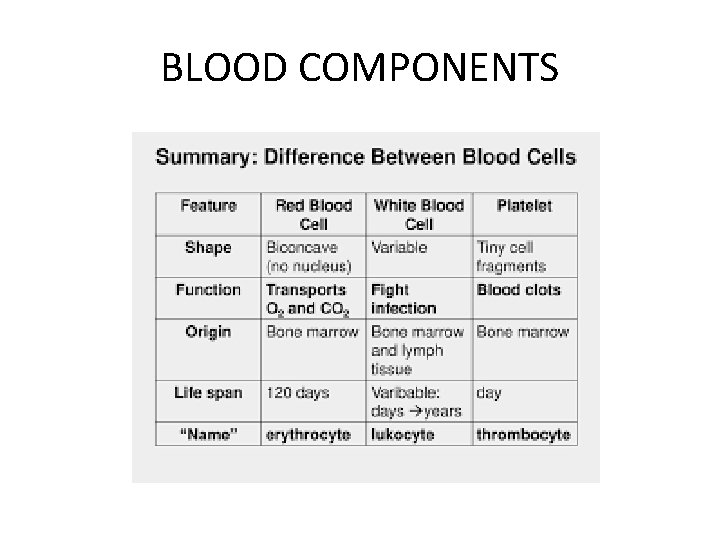

BLOOD COMPONENTS